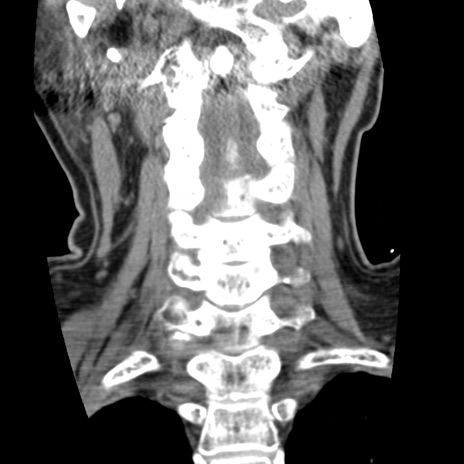

症例50 頚椎CT(冠状断像)

【症例】60歳代女性

【主訴】後頭部〜右後頸部にかけての痛み

【現病歴】本日飲食店でコーヒーを飲んでいたところ、突然後頭部〜右後頸部にかけて痛みが出現し、右上肢の感覚障害を伴ったため救急要請。

【身体所見】脳神経学的に明らかな異常所見を認めず。右上肢に軽度の感覚障害あり。

異常所見と診断は?

頚椎CT